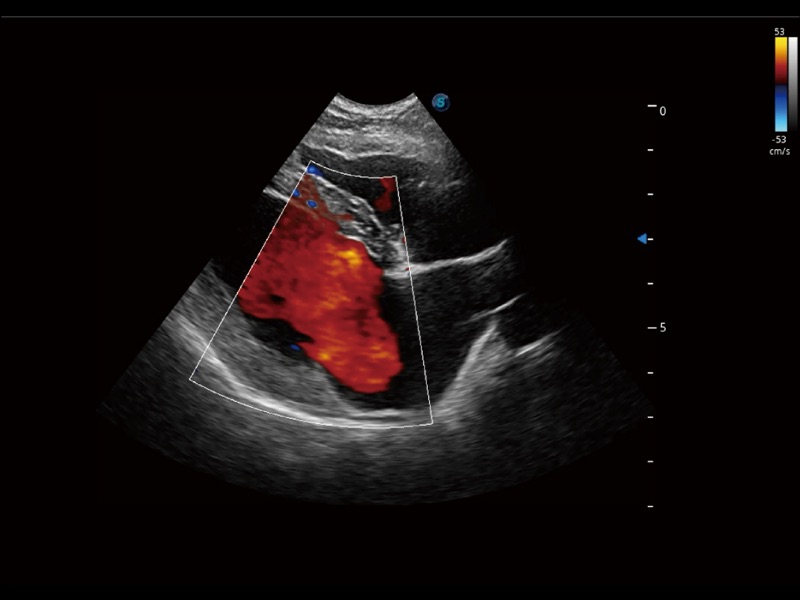

采用红、橙、黄、绿、青、蓝、紫这七种肉眼最为敏感的色彩,直观地显示组织内血流灌注的时间先后信息,更精准捕捉血流灌注走行细节。

通过创新的 Matrix E自适应滤波器和超长时间域算法,极大提升超低速微细血流的检出能力,同时更精准地滤除软组织和噪声信号,为兽用医生提供以往无法通过常规血流获得的疾病诊断信息。